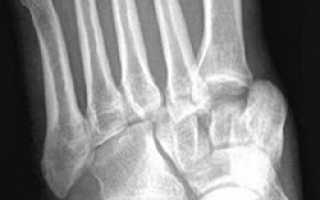

Диагноз устанавливают на основе рентгенограмм в профильной и фасной проекциях. Чтобы избежать ишемических осложнений, диагноз «подтаранный вывих стопы» требует от врача оказания неотложной травматологической помощи. Эта помощь должна учитывать конкретные варианты повреждений подтаранного сустава.

Для уточнения диагноза и выявления сопутствующих повреждений выполняют рентгенографию в двух проекциях. Вывихи, сопровождающиеся повреждением костного и связочного аппарата, считаются тяжелыми. Нормальная функция сустава возможна только при точном восстановлении взаиморасположения отломков.

Подтаранный вывих стопы встречается крайне редко. Он возникает при резком подворачивании стопы и сопровождается разрывом связок, сильной болью, отеком и деформацией. Для уточнения диагноза и исключения переломов проводят рентгенографию.